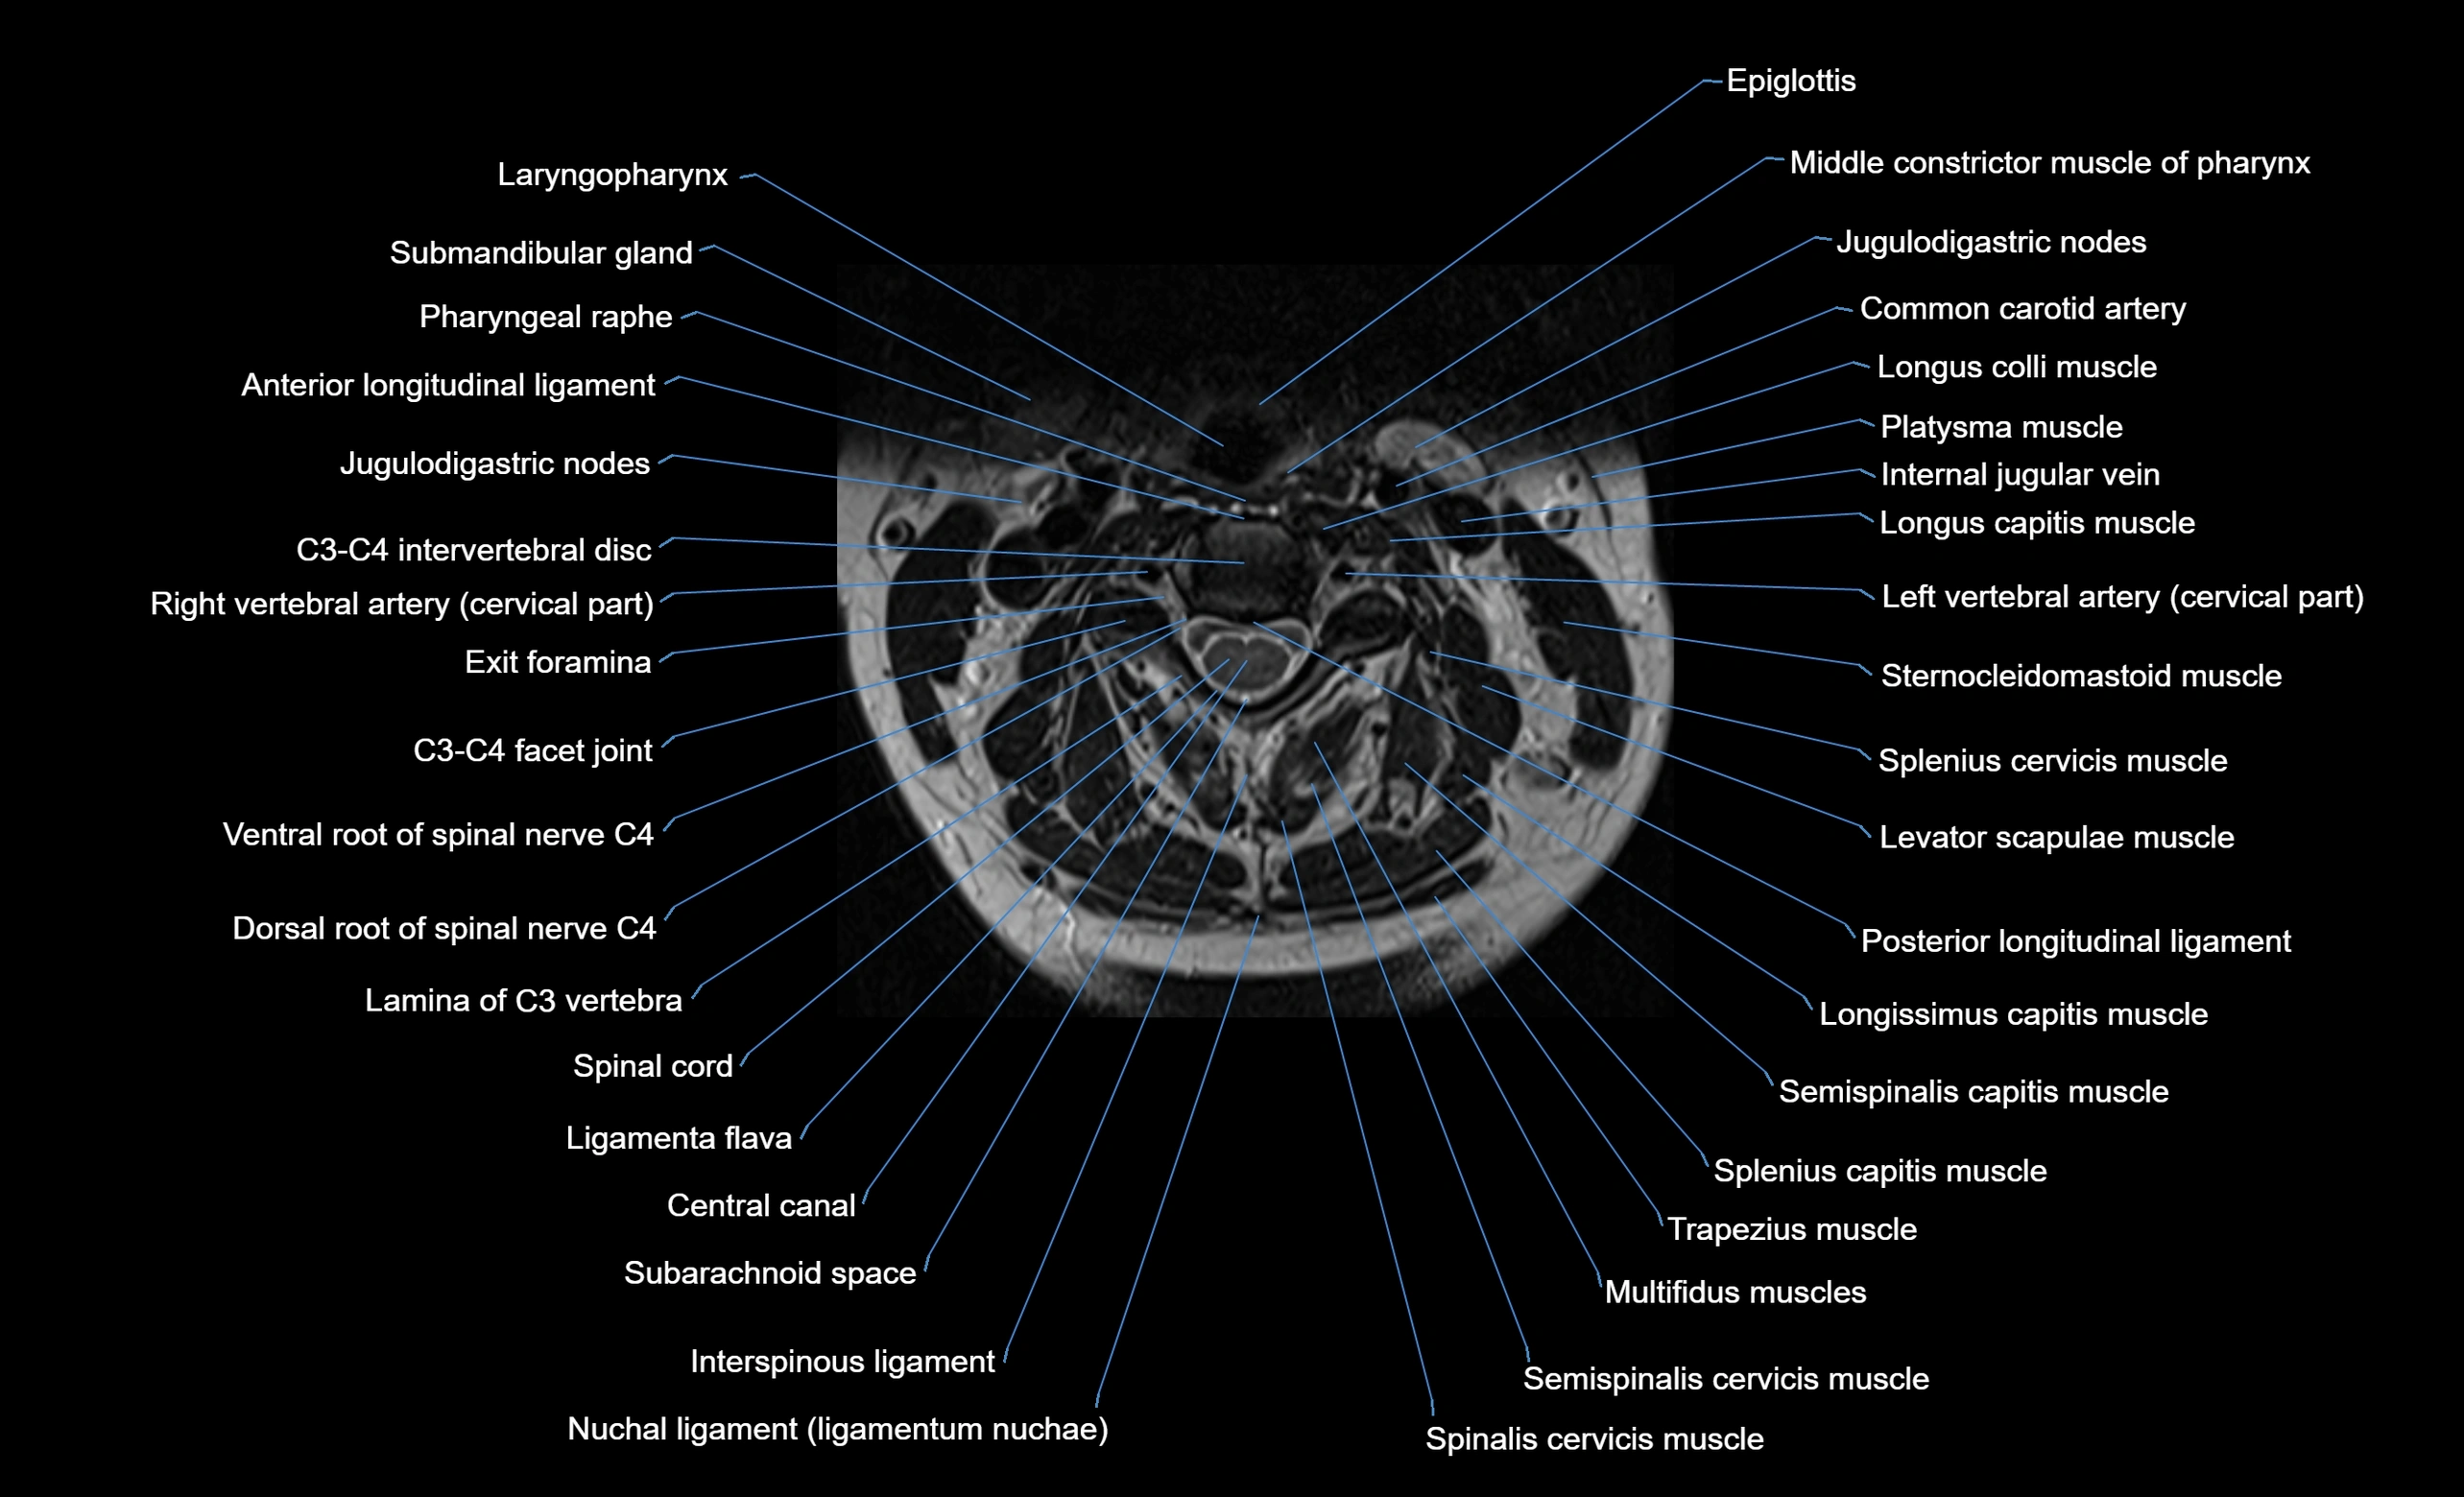

MRI appearance

T1-weighted images:

• Annular epiphysis: Low signal cortical rim at the vertebral margin

• Adjacent marrow: Intermediate-to-high signal in the vertebral body

• Disc interface: Clear delineation between bone and annulus

T2-weighted images:

• Annular epiphysis: Low signal intensity line

• Endplate cartilage (in younger patients): Intermediate signal

• Intervertebral disc: High signal nucleus pulposus

STIR:

• Annular epiphysis: Low signal cortical rim

• Adjacent marrow: Suppressed fat signal with preserved bony outline

• Utility: Highlights marrow and endplate interface in developing spine

MRI image

image